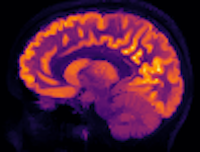

Bayesian Uncertainty Quantification for PET Imaging

The medical imaging technique Positron Emission Tomography (PET) is an important cornerstone in modern medicine allowing non-invasive, sensitive, and specific detection of disease. Small metastases at the edge of the PET resolution limit are difficult to correctly diagnose with the current technology. In this PhD project, we are investigating Bayesian inference, backed by sound mathematical and statistical theory to tackle this problem.